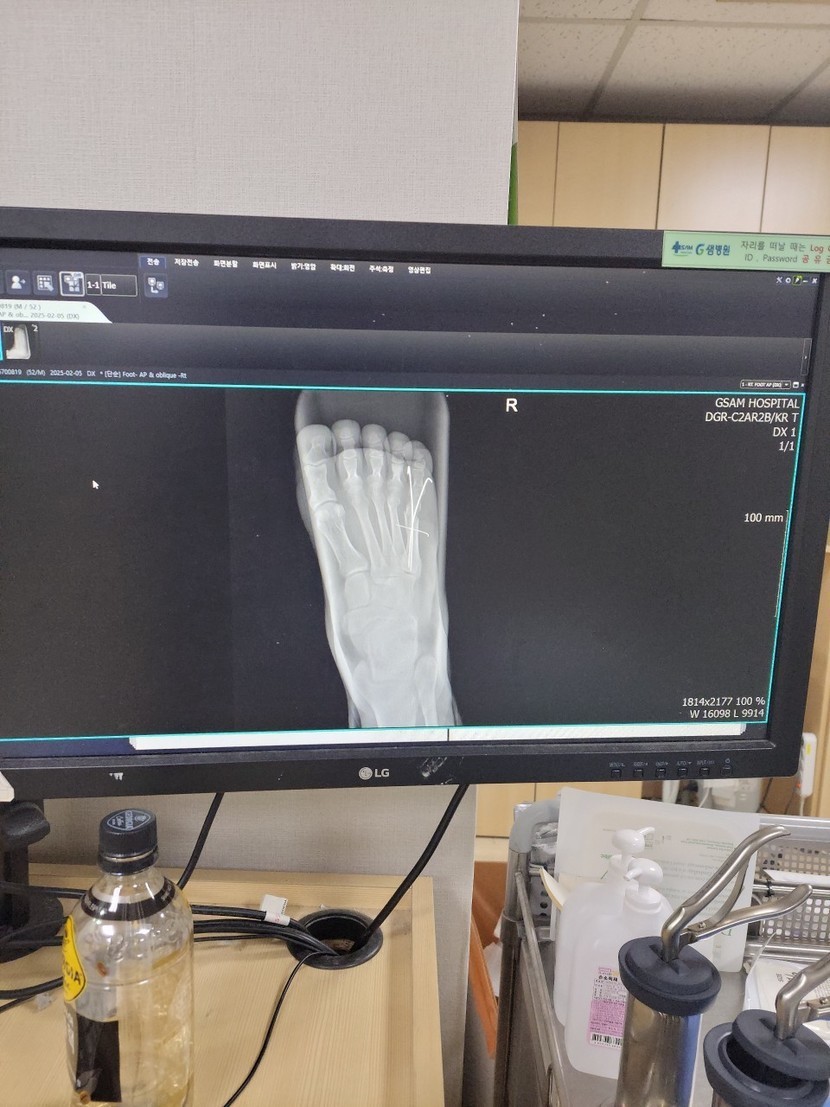

25.02.10 118 읽음 현재 상태 convertkch 구독하기 12 16 콘텐츠의 수익 3 뼈가 붙는게 6~8주라니최소 2월말까지는지금처럼 재택근무하며 버텨야 할듯일주일에 한번내지 두번 통원치료 빼고는집에만 있어야하니 무지 답답하네요.다들 행복한 하루 보내세요 16 0 / 300 입력